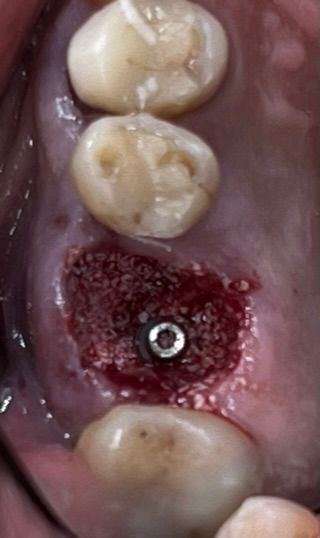

6. Immediate implant placement Ø 6.4mm Axiom® X3, 4 mm deep from the gum margin in the bone furcation for mucointegration.

6

7. Filling gaps with xenograft material

for socket preservation.

7

9. Intra oral view with the SSA in place.

9